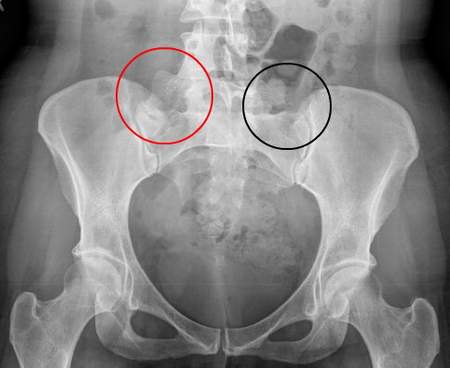

| Viêm khớp cùng chậu 2 bên trên phim Xquang |